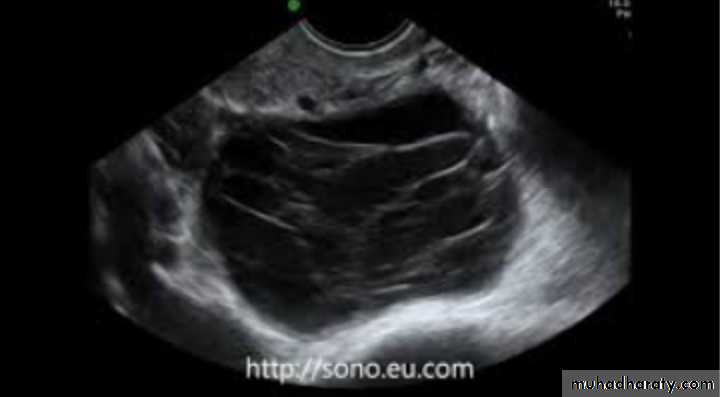

PCOS